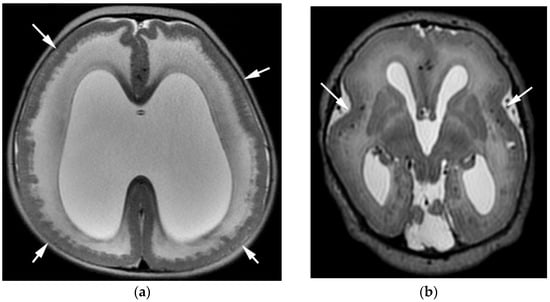

3.2. Cobblestone Cortex